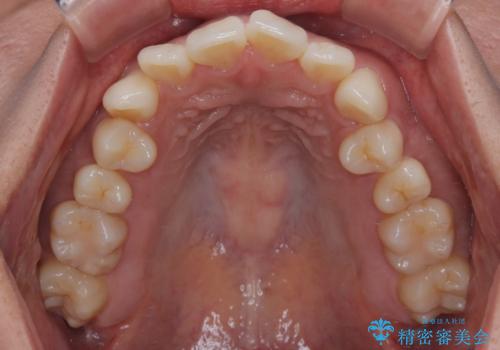

初診時、上下顎ともに歯列の不正が認められ、特に左下の小臼歯が大きく歯列から外れている状態でした。その影響により、下顎の正中が左側へシフトしており、見た目だけでなく噛み合わせにも影響が出ていました。

左下の小臼歯をきれいに歯列内へ並べるためには、まず十分なスペースの確保が必要でした。

そこで本症例では、上顎右側にアンカースクリュー(矯正用インプラント)を埋入し、そこからゴムかけ(顎間ゴム)を行うことで、下顎の正中を右方向へコントロール。

これにより、左下小臼歯がく並ぶためのスペースを確保することができました。